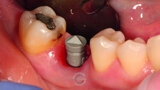

Implant restoration with CEREC